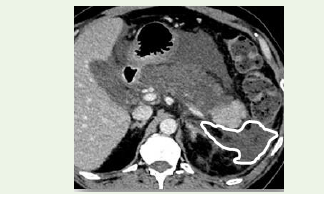

Quantitative volumetric analysis revealed extrapancreatic necrosis volume exceeding 150 mL and significant peripancreatic fluid collections [Figure 4].

The patient developed persistent organ failure requiring ICU admission and underwent percutaneous drainage for necrotic collections. The clinical course was complicated by prolonged hospitalization; however, the patient showed gradual recovery with multidisciplinary management.

This case highlights the strong correlation between increased extrapancreatic necrosis volume and severe disease, emphasizing its role as a reliable imaging biomarker for predicting adverse outcomes.

Figure 4: Three-dimensional volumetric assessment demonstrating

quantitative measurement of extrapancreatic necrosis volume in the

representative severe case using region-growing technique [8,12]